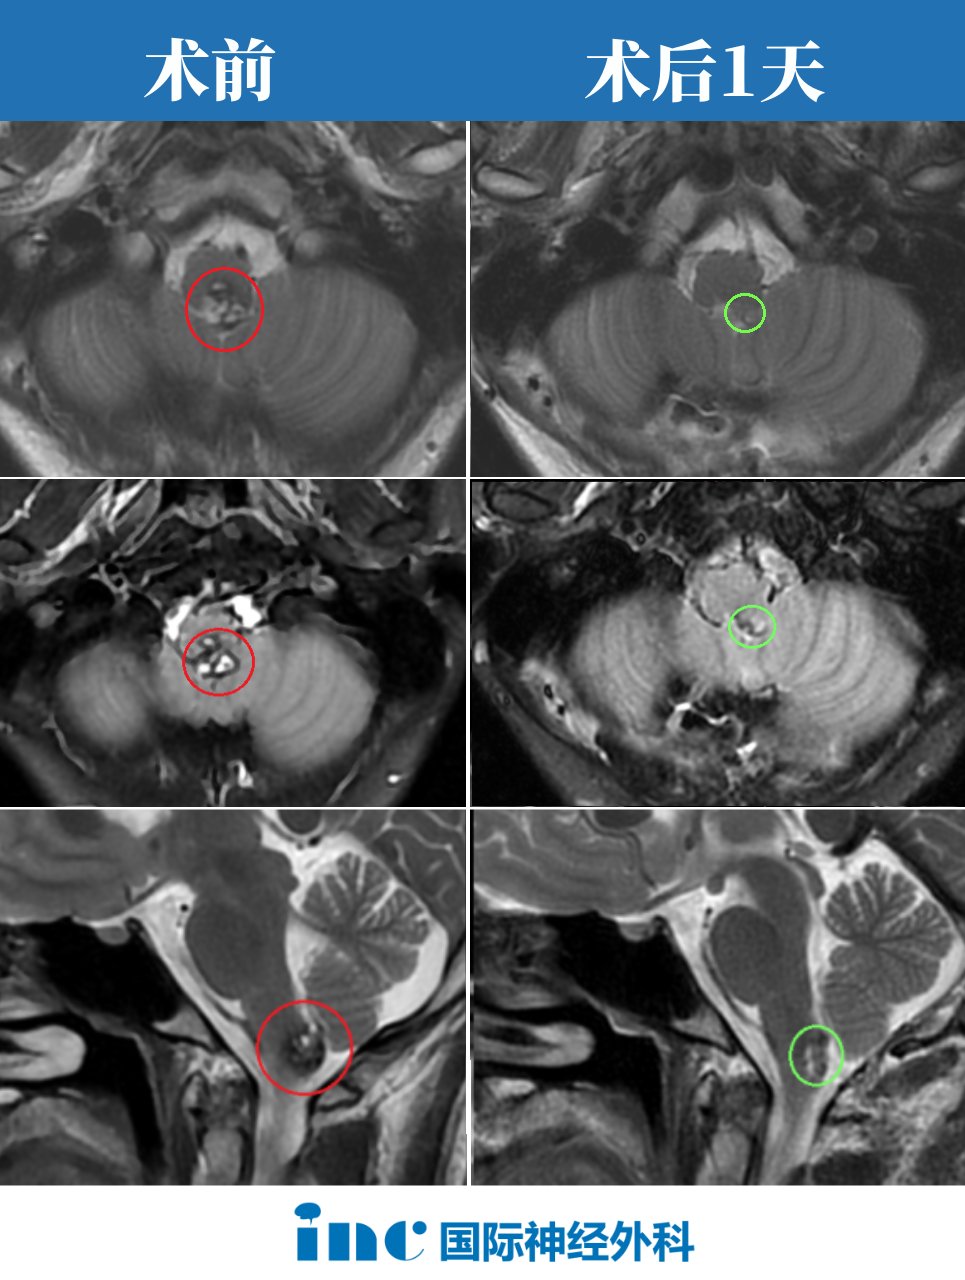

脑干延髓是心跳、呼吸等关键生命中枢,神经核团高度密集,脑干海绵状血管瘤有反复出血造成肢体瘫痪、呼吸困难无力甚至昏迷等风险,手术一直以来都是难题。

整个做完以后包括片子拍出来以后,我也给我们那的神经外科医生看。一看,他说:唉呀,真的很神奇,做的这么干净,做的这么好。关键是恢复的也这么快,1天就出ICU了,而且神志这么清晰。我儿子就继续给他打电话,他说不可能吧。

术后第一天巴教授ICU查房,阿朔意识清楚、对答入流、四肢活动灵活

阿朔手术直播中,在术中神经电生理监测下,巴教授顺利全切取出肿瘤